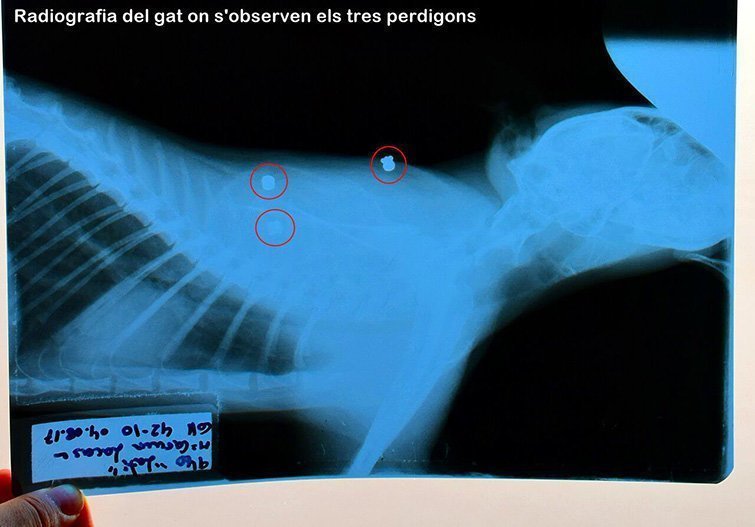

Els fets haurien passat el 4 d'agost al voltant de les 8 del matí quan l'home suposadament va disparar des de la seva terrassa un dels gats que era al pati de la veïna. La dona, Mari Carme Lacasa, ha explicat que el gat va caure ferit i en aquell moment va veure el presumpte autor dels trets amb l'arma a la mà. Segons Lacasa, "no és la primera vegada que ho fa" i, de fet, la denúncia recull que en els dos últims anys han mort una desena de gats per trets o enverinats i en tots els casos se sospita que el responsable és la mateixa persona. La dona ha comentat que les denúncies anteriors no van tirar endavant per falta de proves. En aquest cas, a la denúncia s'hi ha incorporat l'informe veterinari que constata que el gat tenia tres perdigons en diferents parts del cos.